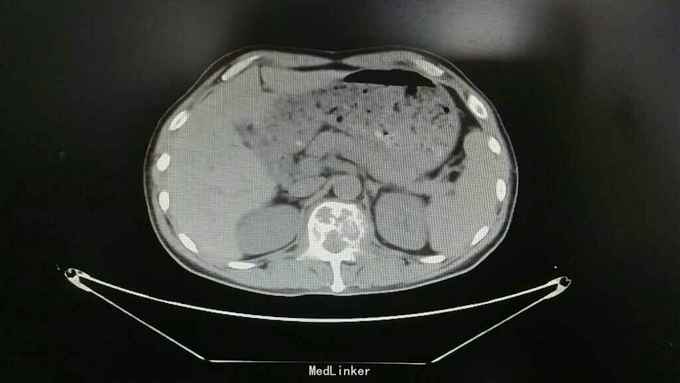

查体:脊柱生理曲度存在,无明显前凸,侧弯或后凸畸形,约胸10至腰5节段压痛及叩击痛阳性,双下肢肌张力正常,双侧股四头肌肌力约三级,双侧足背伸肌,踇背伸肌肌力约四级,双侧“4”字试验阴性,双侧直腿抬高试验阴性。肛周约15cm范围皮肤感觉减退。 辅助检查:肿瘤标志物无明显异常,血沉达120mm/h,血红蛋白111g/l,球蛋白与白蛋白比值倒置,血免疫球蛋白IgG达46.2g/l,明显升高。血清Kappa轻链与血清Lambda轻链比值明显升高。余辅助检查见下图。

通过影像学,实验室检查,骨髓穿刺检查及行CT引导下穿刺病理结果,患者多发性骨髓瘤诊断已明确。于全麻下行“腰1椎体病理性骨折病变清除减压内固定术”,术中可见病变压迫脊髓明显,彻底减压,术中出血较多,椎体破坏较重,未予骨水泥塑型,术后患者症状缓解明显,拆线后转至血液科进一步治疗。

多发性骨髓瘤是一种单克隆的浆细胞异常增生所致的恶性肿瘤,常以骨骼症状为首发,以脊柱最常累及,本例患者主要手术指征为持续且无法缓解的骨痛,并存在脊髓和神经根压迫症状,,主要影像学表现为穿凿样溶骨性改变,周围无硬化改变。很多全身骨现象无明显的阳性表现,增加了诊断的难度,上面提到的血沉升高,贫血,球白比倒置,血免疫球蛋白升高,骨髓穿刺综合判断,诊断明确后,一般行姑息性手术治疗,一般预后较差,随访见到生存期最长为4年。